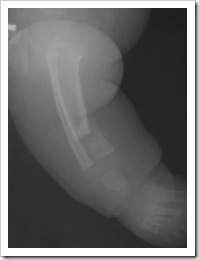

- Typ IV - (dysplastyczny) – najgorsze rokowanie, zagięcie przednio-boczne ze złamaniem i stawem rzekomym, z wrzecionowatym zwężeniem kości w obrębie stawu rzekomego, z całkowitym lub częściowym zamknięciem kanału szpikowego.

- śródszpikową stabilizację (gwoździe blokowane, pręty endera, TEN) Jeśli staw rzekomy jest blisko nasady do rozważenia jest założenie wszczepu śródszpikowego przezpiętowo. Zyska się w ten sposób dodatkową stabilność fragmentu dystalnego jednak kosztem późniejszych zaburzeń w obrębie stawu skokowego (Obu)